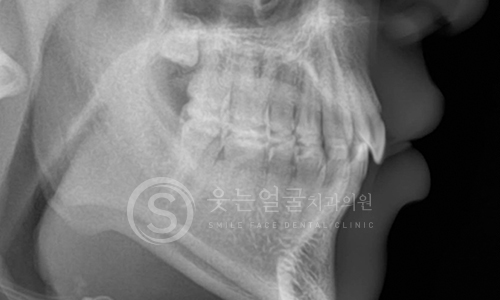

8천여건의 다양한

임플란트 수술 케이스

다년간 축적된 8,000여 건 이상의

임플란트 수술 경험을 바탕으로,

환자 개개인의 구강 구조와

상태에 최적화된 안전하고 정확한 시술을 제공합니다.